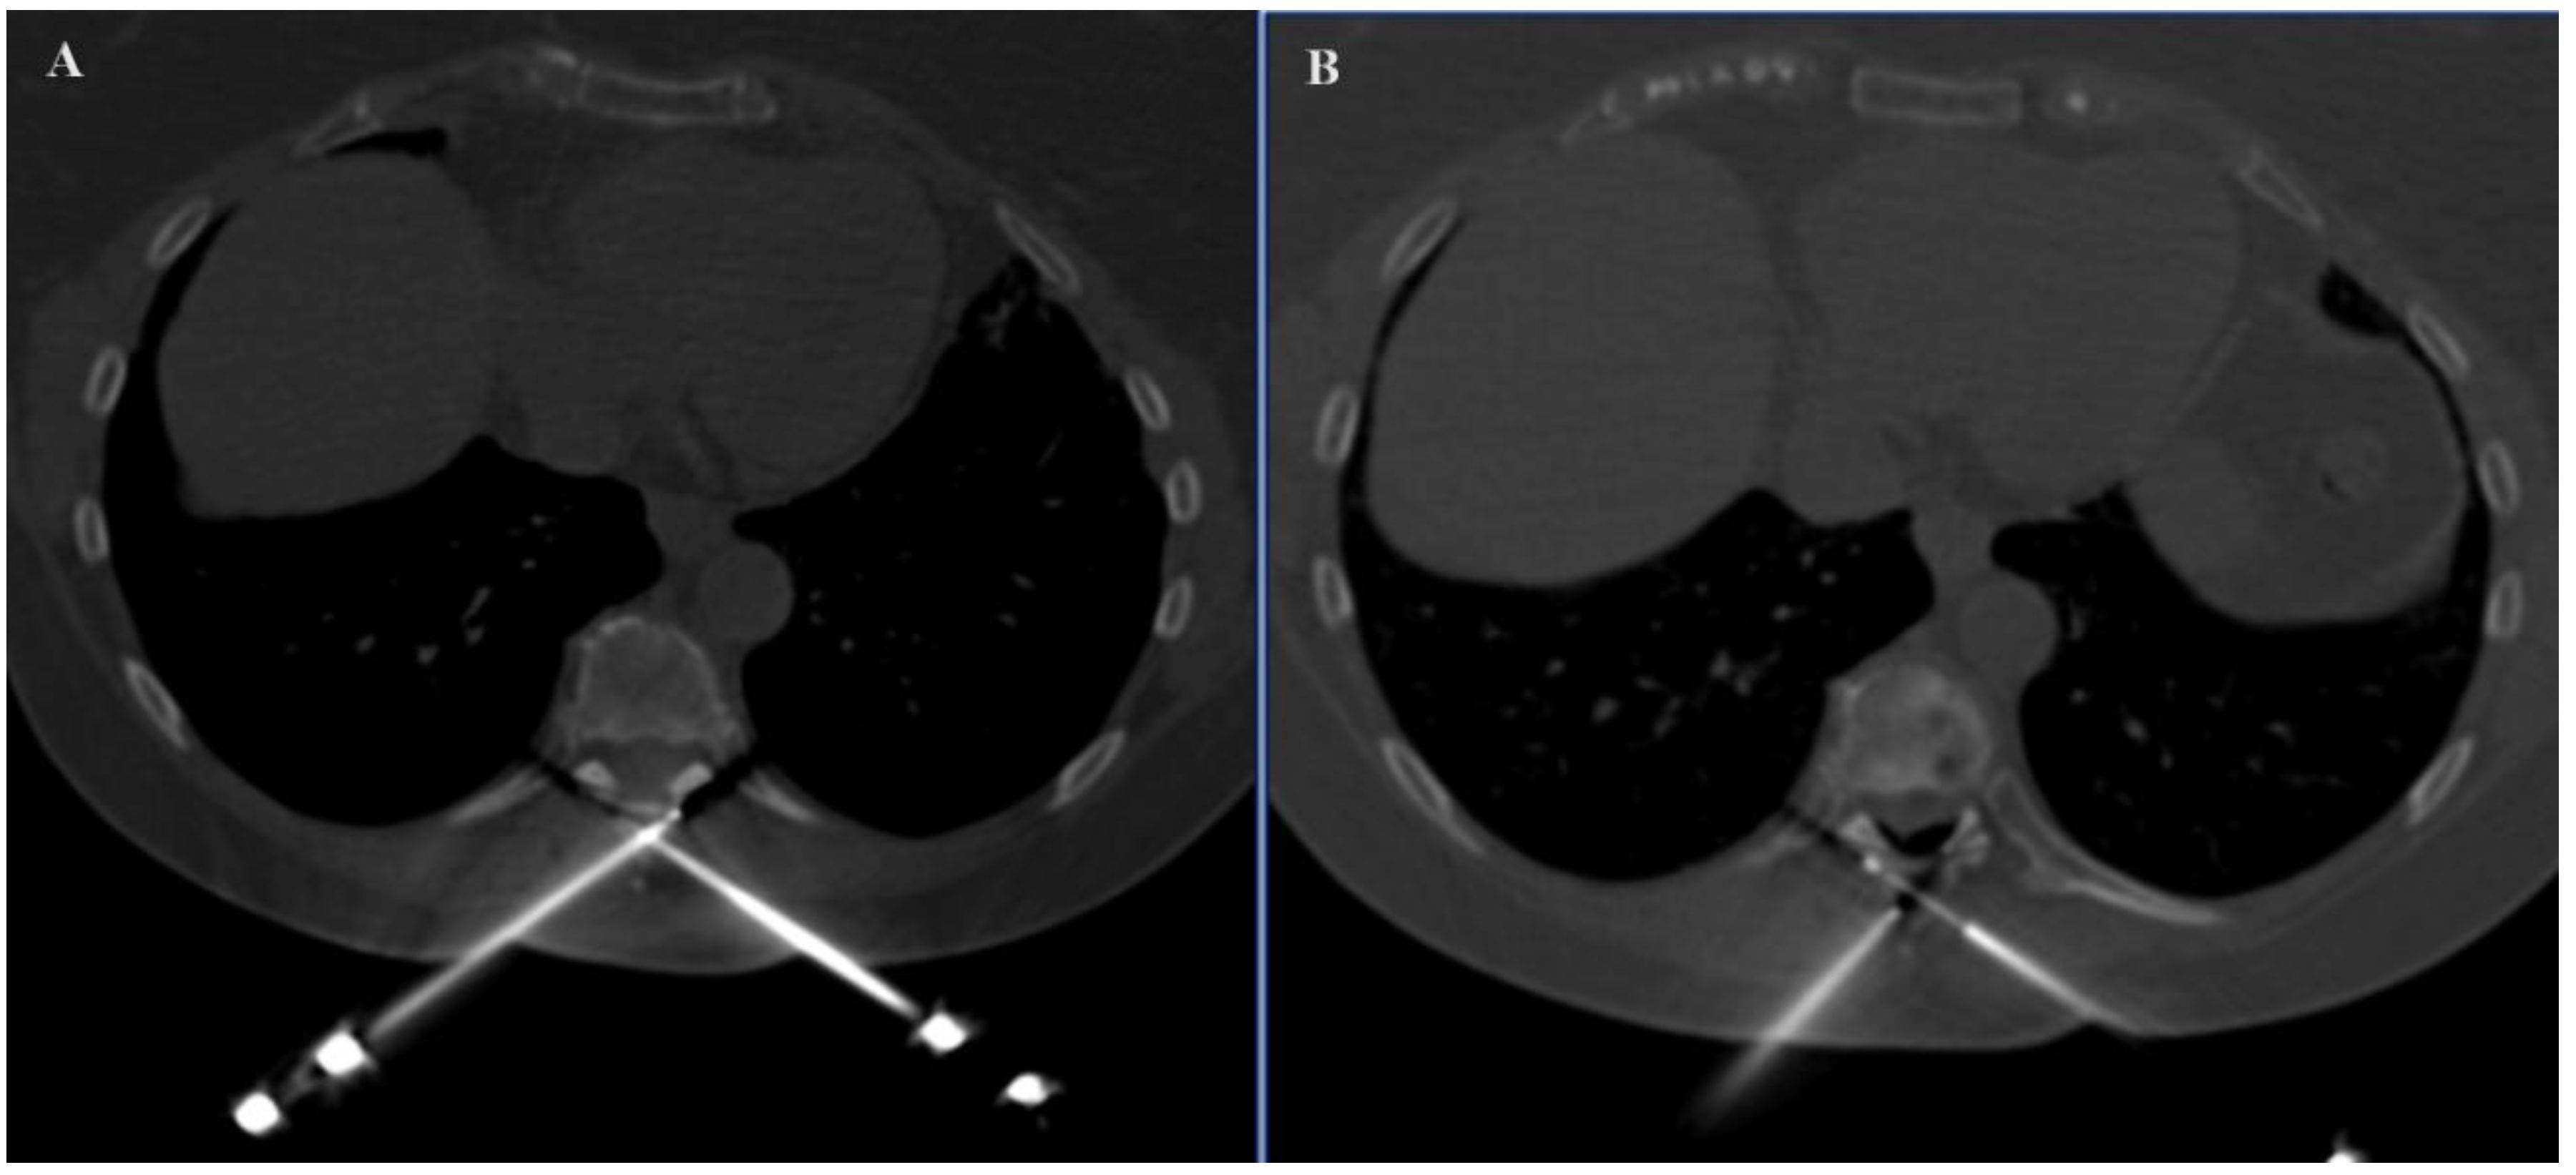

In the SIRIO-assisted group, the SIRIO augmented reality navigation system was used to guide the needle into the lesion with real-time 3D visualization. Standard CT guidance was employed in the non-SIRIO group. Epidural dissection was performed in all procedures through a 22 G needle, using non-ionic 5% dextrose mixed with diluted organ iodine contrast medium and carbon dioxide (Figure 1 and Figure 2), to obtain a multilevel dissection adjacent to the site to be treated. The procedures were performed under similar conditions, with a focus on minimizing radiation exposure and ensuring precision in needle placement. For each patient, medical records, previous imaging exams, laboratory studies, and lesion-related pathological information were carefully evaluated.

Figure 2. Axial images demonstrating the positioning of two probes in the spinal process of D8 (A) and the adjacent epidural dissection obtained (B).